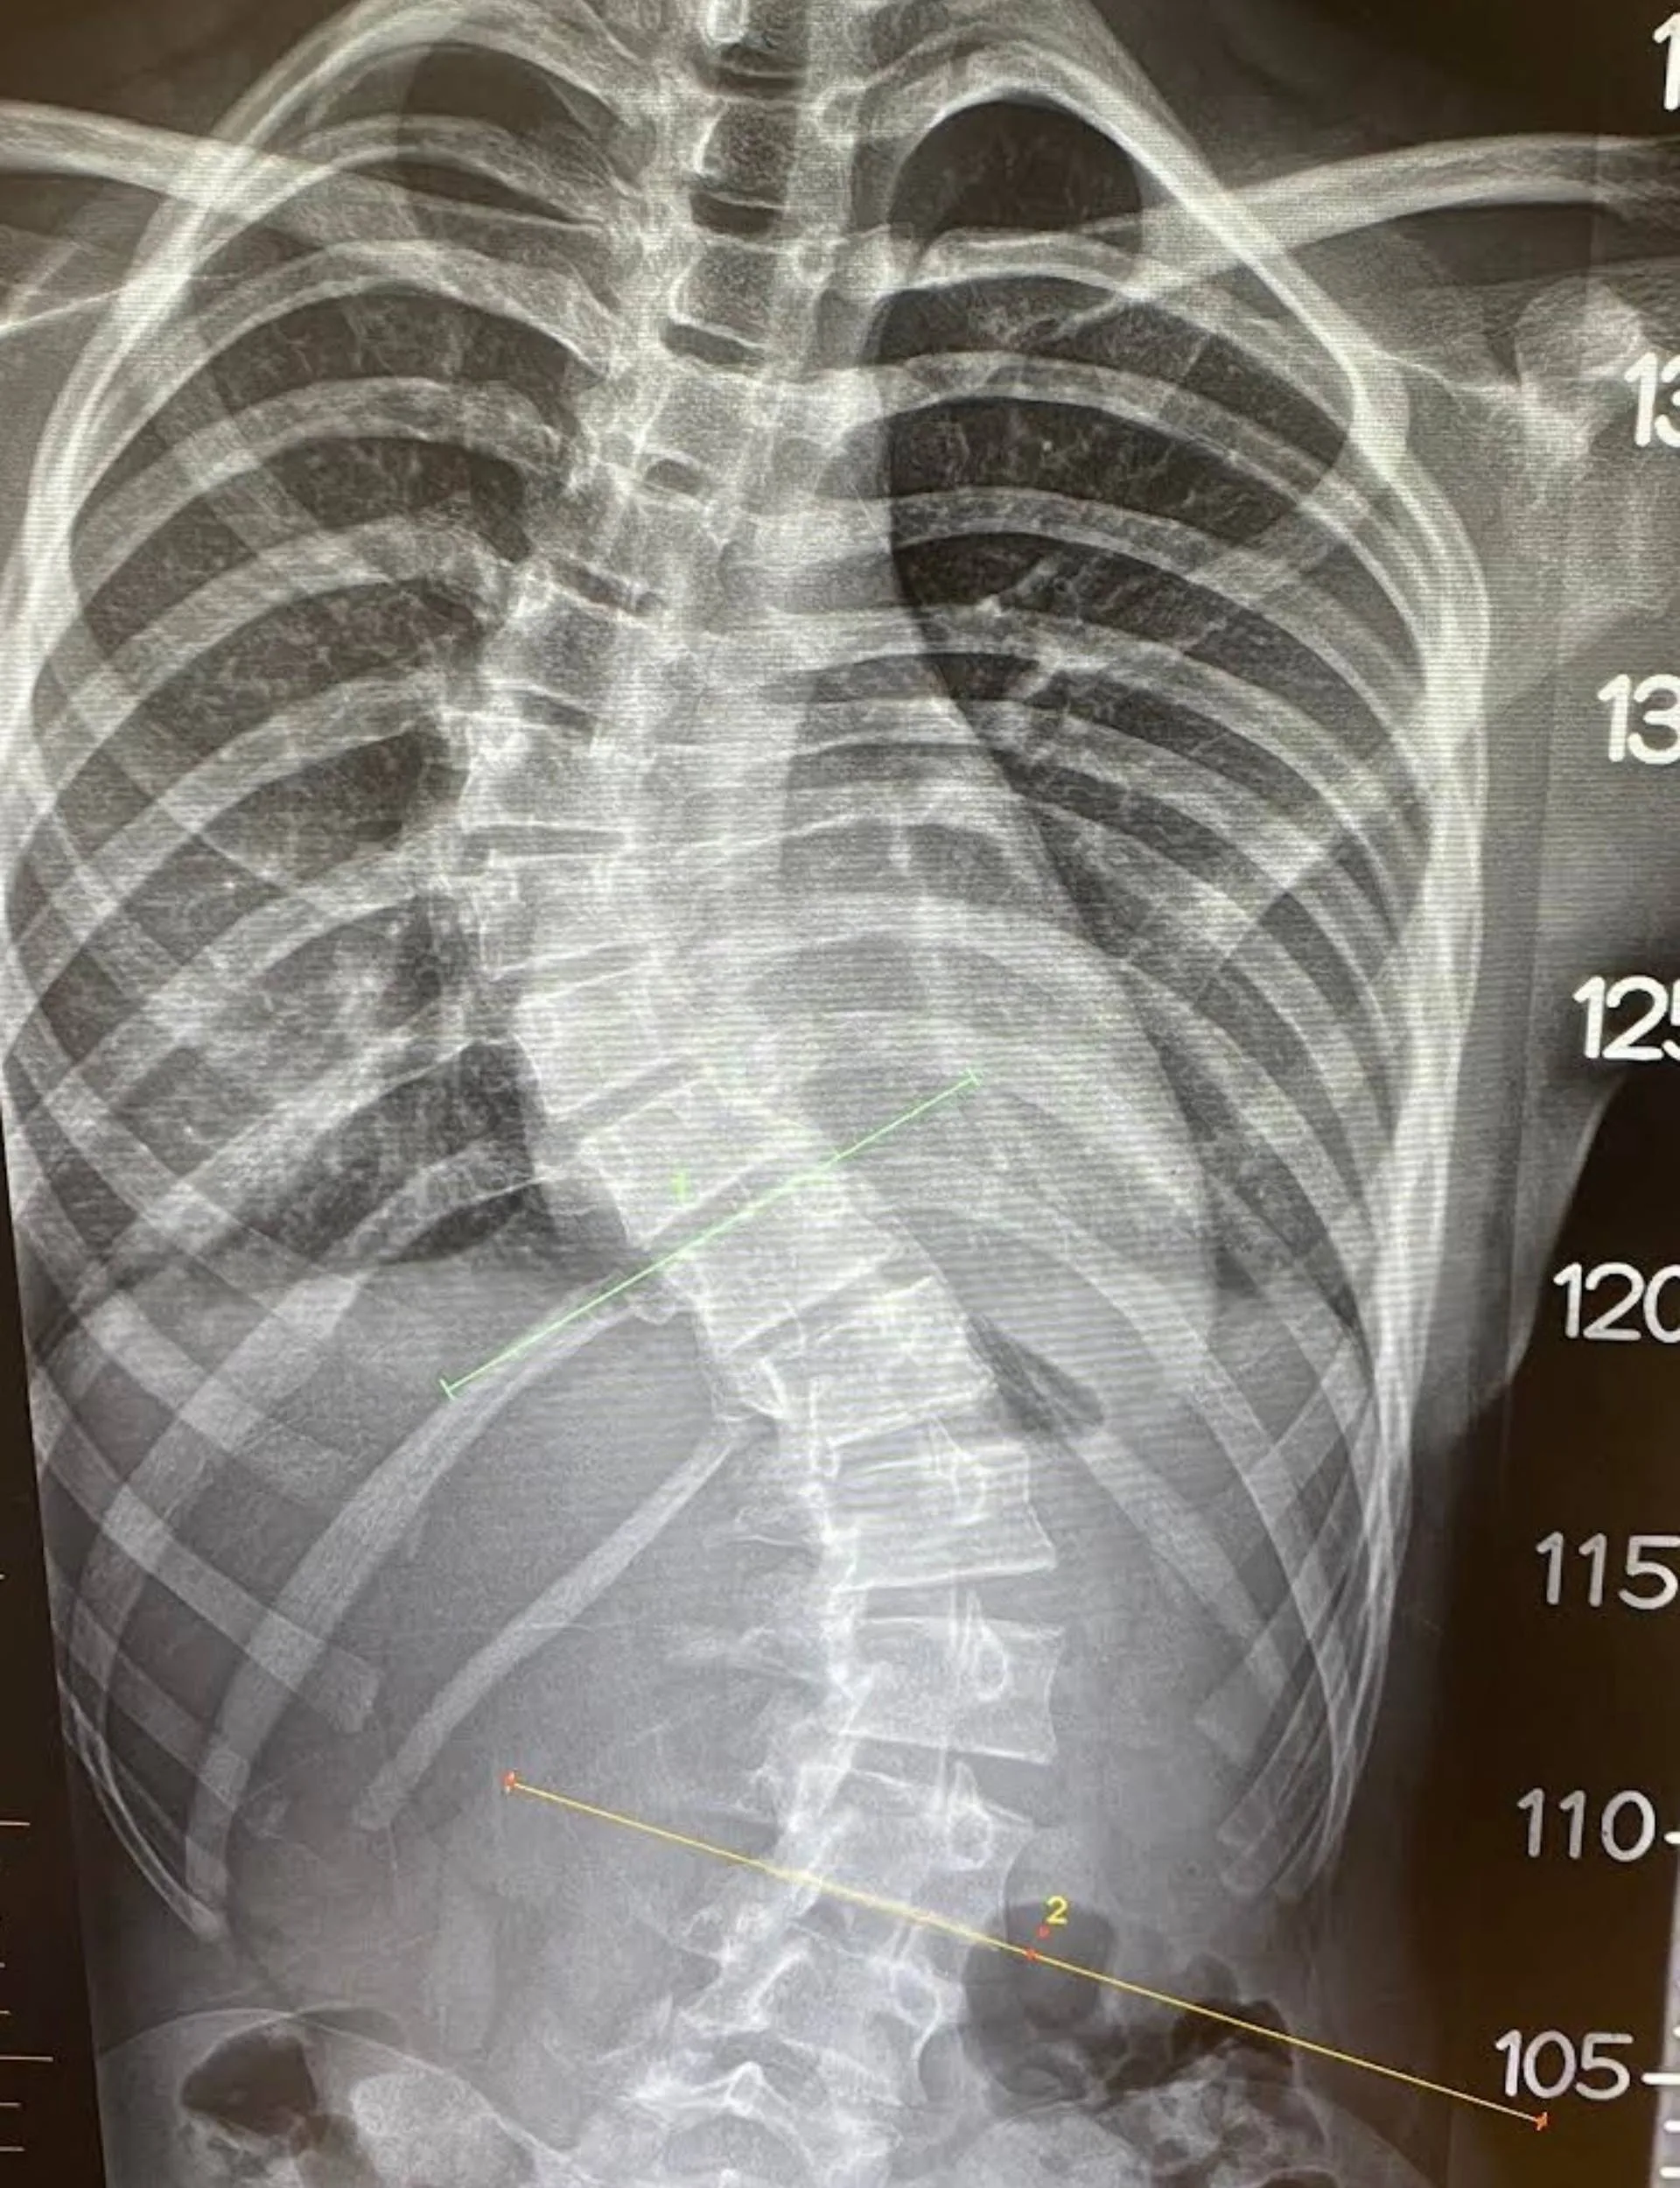

This is because Harlin has severe idiopathic scoliosis. Where the spine is traditionally straight, Harlin’s features an “S” curve. X-rays show there’s a 56-degree bend in the worst of the two places. The naked eye can detect it too, which Harlin’s aware of.

“When the doctors showed us the X-ray of my spine, I was shocked and kind of sad.”